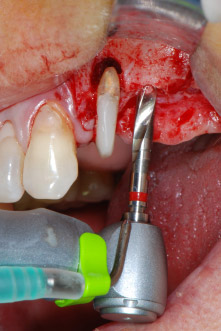

Zunächst wurde in einem Versuch, das Paro-Endo-Problem zu lösen, an der verbleibenden Wurzeloberfläche ein vorsichtiges Debridement mit einem piezochirurgischen Gerät vorgenommen (Piezomed, W&H) (Abb. 4); dann wurde der Apex mit dem gleichen Instrument im Sinne einer WSR abgetragen, um das verbleibende infizierte apikale Gewebe zu entfernen (Abb. 5). Eine retrograde Füllung war nicht notwendig, da die orthograde Füllung gerade revidiert worden war.